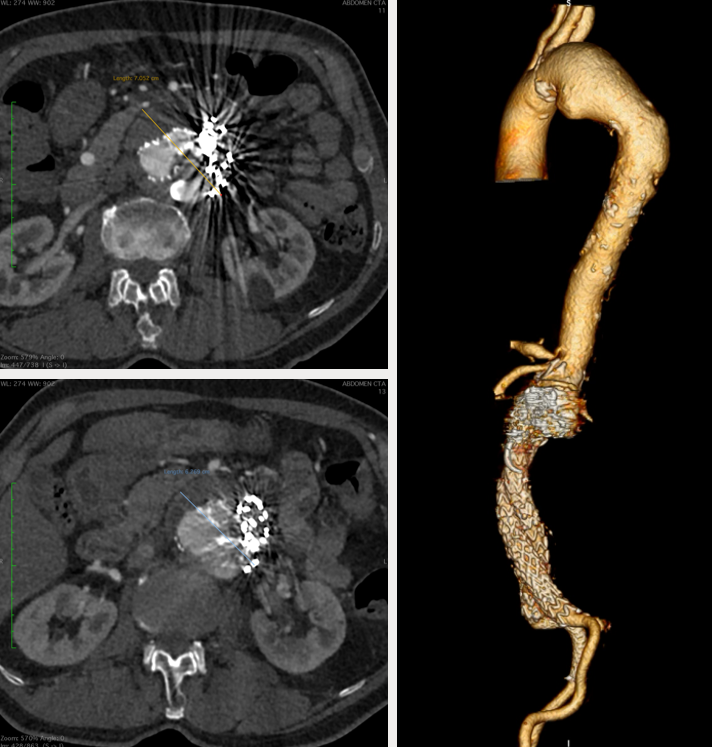

77岁男性,腹主动脉瘤EVAR后2年,再发腹痛入院。

既往:腹主动脉瘤,外院4次腔内手术史

2022年8月12日:EVAR+双肾动脉烟囱支架重建

2023年3月24日:CT随访发现Ia型内漏,瘤腔弹簧圈栓塞+生物蛋白胶注射

诊断:术后CT复查Ia型内漏持续,动脉瘤2个月增大7mm

手术难点:

入路扭曲狭窄,双侧髂支多枚补救性裸支架

双肾动脉烟囱支架受裸架压迫紧贴主动脉后壁,左肾动脉烟囱支架打横

裸架丝遮挡SMA开口

弓部动脉瘤

治疗方案:PMEG拓展近端锚定区,重建CA、SMA、RRA和LRA